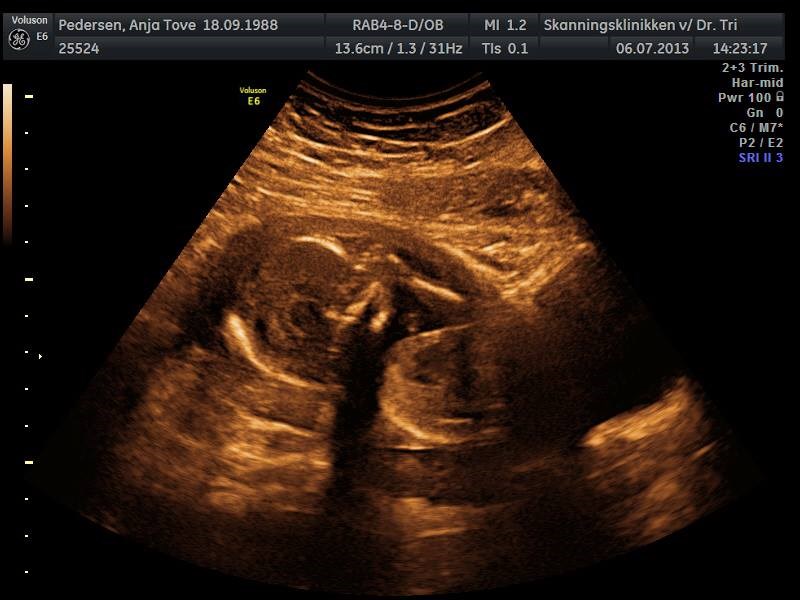

Helt igennem perfekt DRENG

Han er lige præcis som han skal være, dog ikke en særlig fotogen dreng  Han gemte sig hver gang vi troede der var et godt billed, men det betyder bare at vi har fået en masse billeder og en masse filmklip af ham

Da hun skulle se kønnet fik hun lige skyggen af en tissemand, men hurtigt fik lilledrengen en hånd ned på den, for den skulle vi i hvert fald ikke se  Men efter lidt tid viste han dog den stolt frem alligevel

Ud over det så vi ham sutte på tommelfinger og på hans storetå og vi så ham have hikke  Og så var der bare så meget bevægelse i ham, fantastisk at se  Vi fik også et glimt af ham i 3d, men han ville ikke være med til det så vi så kun lidt bevægelse og et halvt ansigt

Nå, men nu kan i da lige få et billede hvor der i hvert fald ikke er tvivl